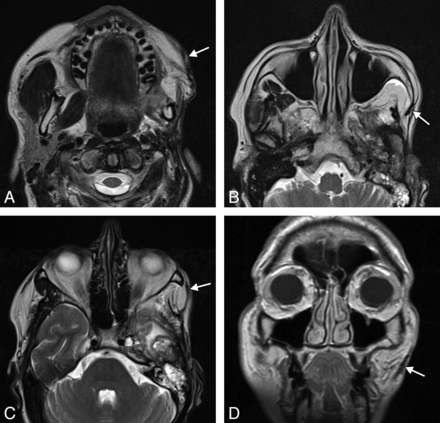

The temporalis flap (temporalis muscle transposition) procedure is an effective option for reanimation of the smile.22 An approximately 1.5-cm-wide strip of the midportion of the temporalis muscle is dissected off the calvaria and reflected in the subdermal plane from the zygomatic arch to the modiolus of the oral commissure (Fig 14). The course of the transposed temporalis muscle can be delineated on cross-sectional imaging as a thin band of soft tissue (Fig 15).

Temporalis flap. Axial T2 MR imaging (A–C) and coronal T1 MR imaging (D) show that the left temporalis muscle with the overlying fascia (arrows) is directed retrograde from the temporal fossa to the orbicularis oris.